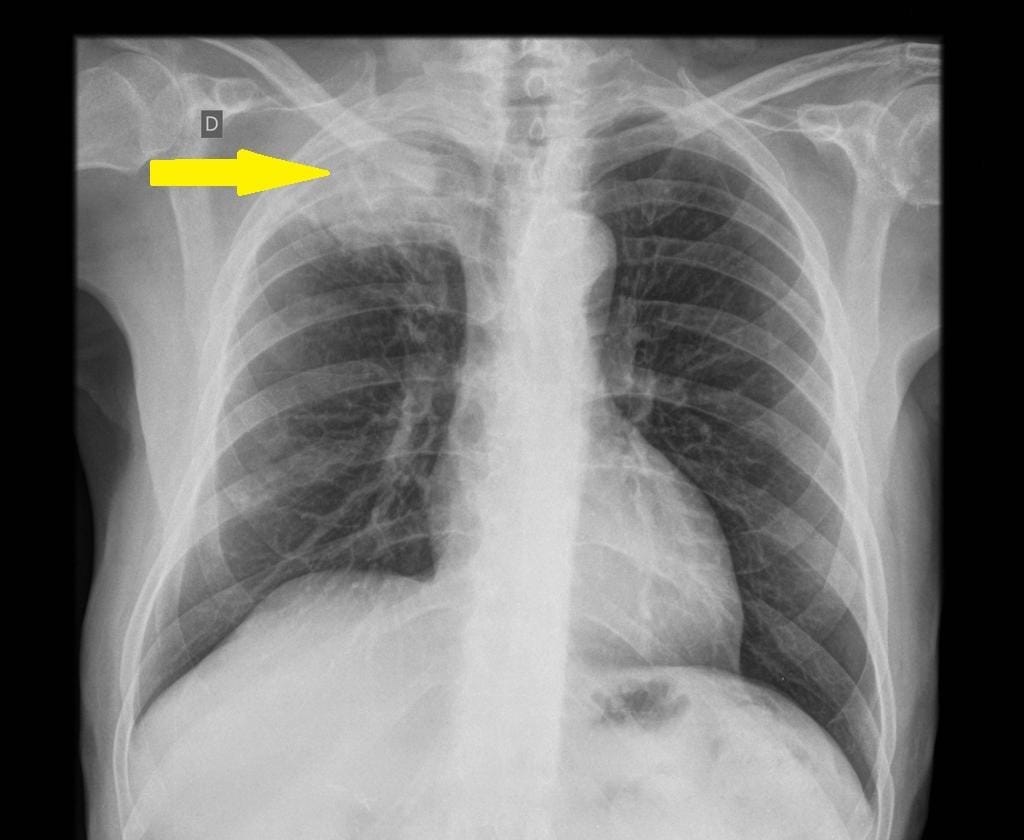

Pancoast tumors (PT) are defined as tumors that invade any of the structures at the apex of the chest, including the first rib or periosteum, the lower nerve roots of the brachial plexus, the sympathetic chain near the apex of the chest, or the subclavian vessels. Pancoast tumors occur in the apical portion of the lung, representing 3%–5% of all lung cancers.

Pancoast tumor is also known as a superior sulcus tumor. Histopathologically, these tumors are commonly adenocarcinomas, and less frequently, squamous call cancer. [1]